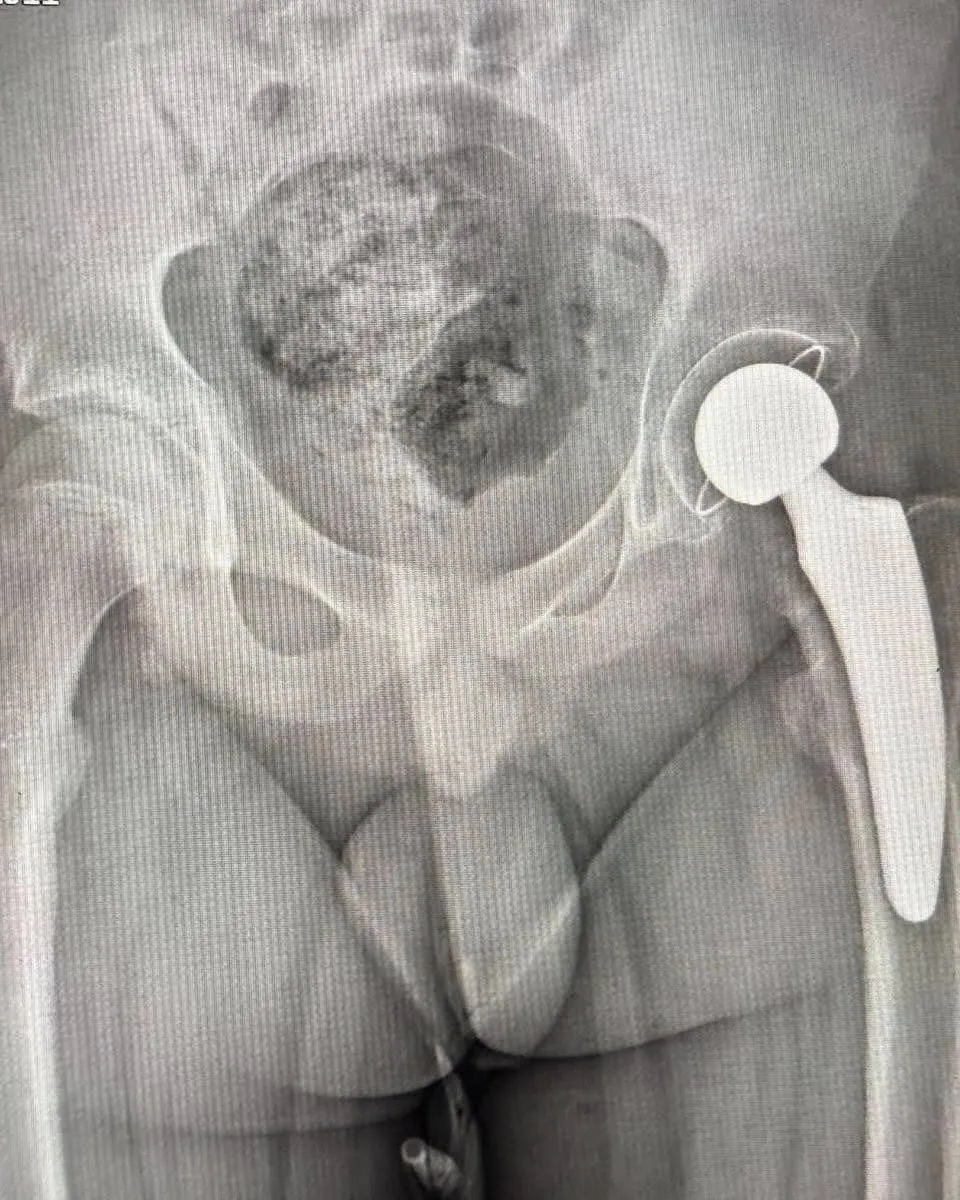

13-річний Михайло з Рахівщини страждав від сильного болю та мав укорочення ноги на 3 см через асептичний некроз, який розвинувся після попередньої операції.

Лікарі Михайло Василинець та В’ячеслав Мотря у складі операційної бригади провели складне тотальне безцементне ендопротезування кульшового суглоба, використовуючи спеціальний протез найменшого розміру. Якщо в майбутньому знадобиться корекція, цей протез можна буде замінити на більший без ускладнень.

Зазвичай такі операції дітям проводять не раніше 15 років, але у випадку Михайла зволікання могло призвести до ще більшого укорочення ноги, проблем із хребтом та значного погіршення якості життя.